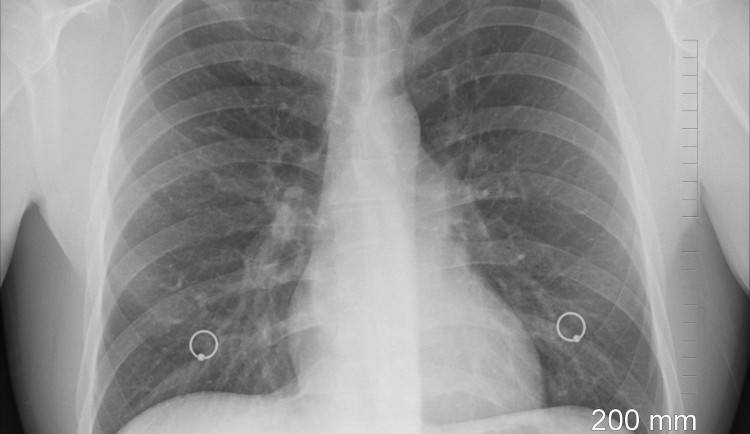

Všeobecná fakultní nemocnice se tento týden zapsala do zdravotnických statistik. Lékaři z pražské nemocnice dokázali udržet pacientku na umělé plíci 143 dní. Světový rekord byl do té doby 79 dní. První český bypass obcházející plíce zachránil šestatřicetileté ženě s těžkou hypertenzí život.

Šestatřicetiletá matka dvouleté holčičky byla do nemocnice převezena v prosinci loňského roku s masivním chrlením krve z plic a selháváním srdce. Na náročnou transplantaci čekala kvůli nedostatku dárců, své málo běžné krevní skupině a strachu lidí z nákazy v době koronavirové epidemie.

„Po zavedení mimotělní membránové oxygenace přistoupili zdejší odborníci k unikátní metodě vyřazení plic z oběhu a využití umělé mimotělní plíce. Podobná operace se za posledních deset let přitom provedla jen u zhruba dvaceti pacientů na světě. V Čechách se jednalo o naprostý unikát,“ popsala nemocnice.

Stav ženy byl zpočátku tak těžký, že byla transplantace neuskutečnitelná. Pacientka proto dostala bypass, který obcházel její plíce. „Umožnili jsme jí žít s mimotělní plící pověšenou na hrudníku, aby její tělo mělo určitý čas se zotavit a připravit na budoucí transplantaci plic, která byla její jedinou perspektivou,“ popsal vedoucí lékař kliniky anestezie a resuscitace Všeobecné fakultní nemocnice Martin Balík.